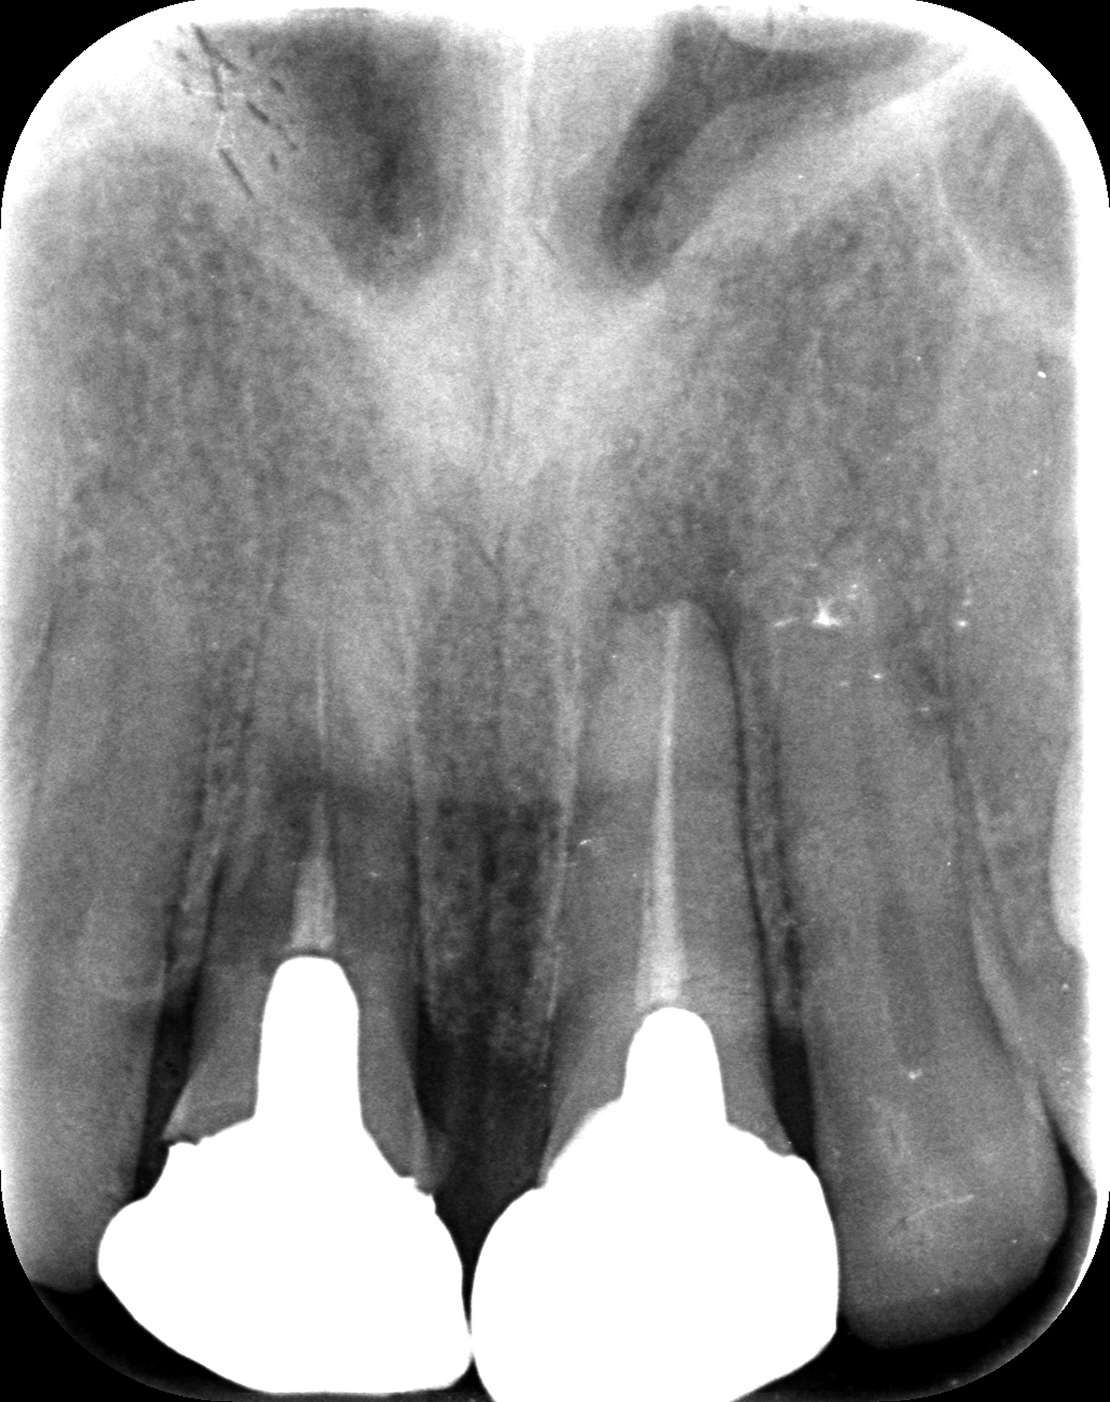

お口全体を検査したところ、自覚はありませんでしたが、右の前歯もレントゲンを見ると歯の根の中腹あたりが溶けてしまっています。この歯も残念ながら抜歯となると判断しました。

左上は歯の周りに骨が全然なかったので抜歯後に骨を作る処置(GBR)を行いました。

緑部分が作った骨になります。半年間待ちましたが、これがないと仕上がりが長い歯になってしまい、すごく見た目が悪くなってします。